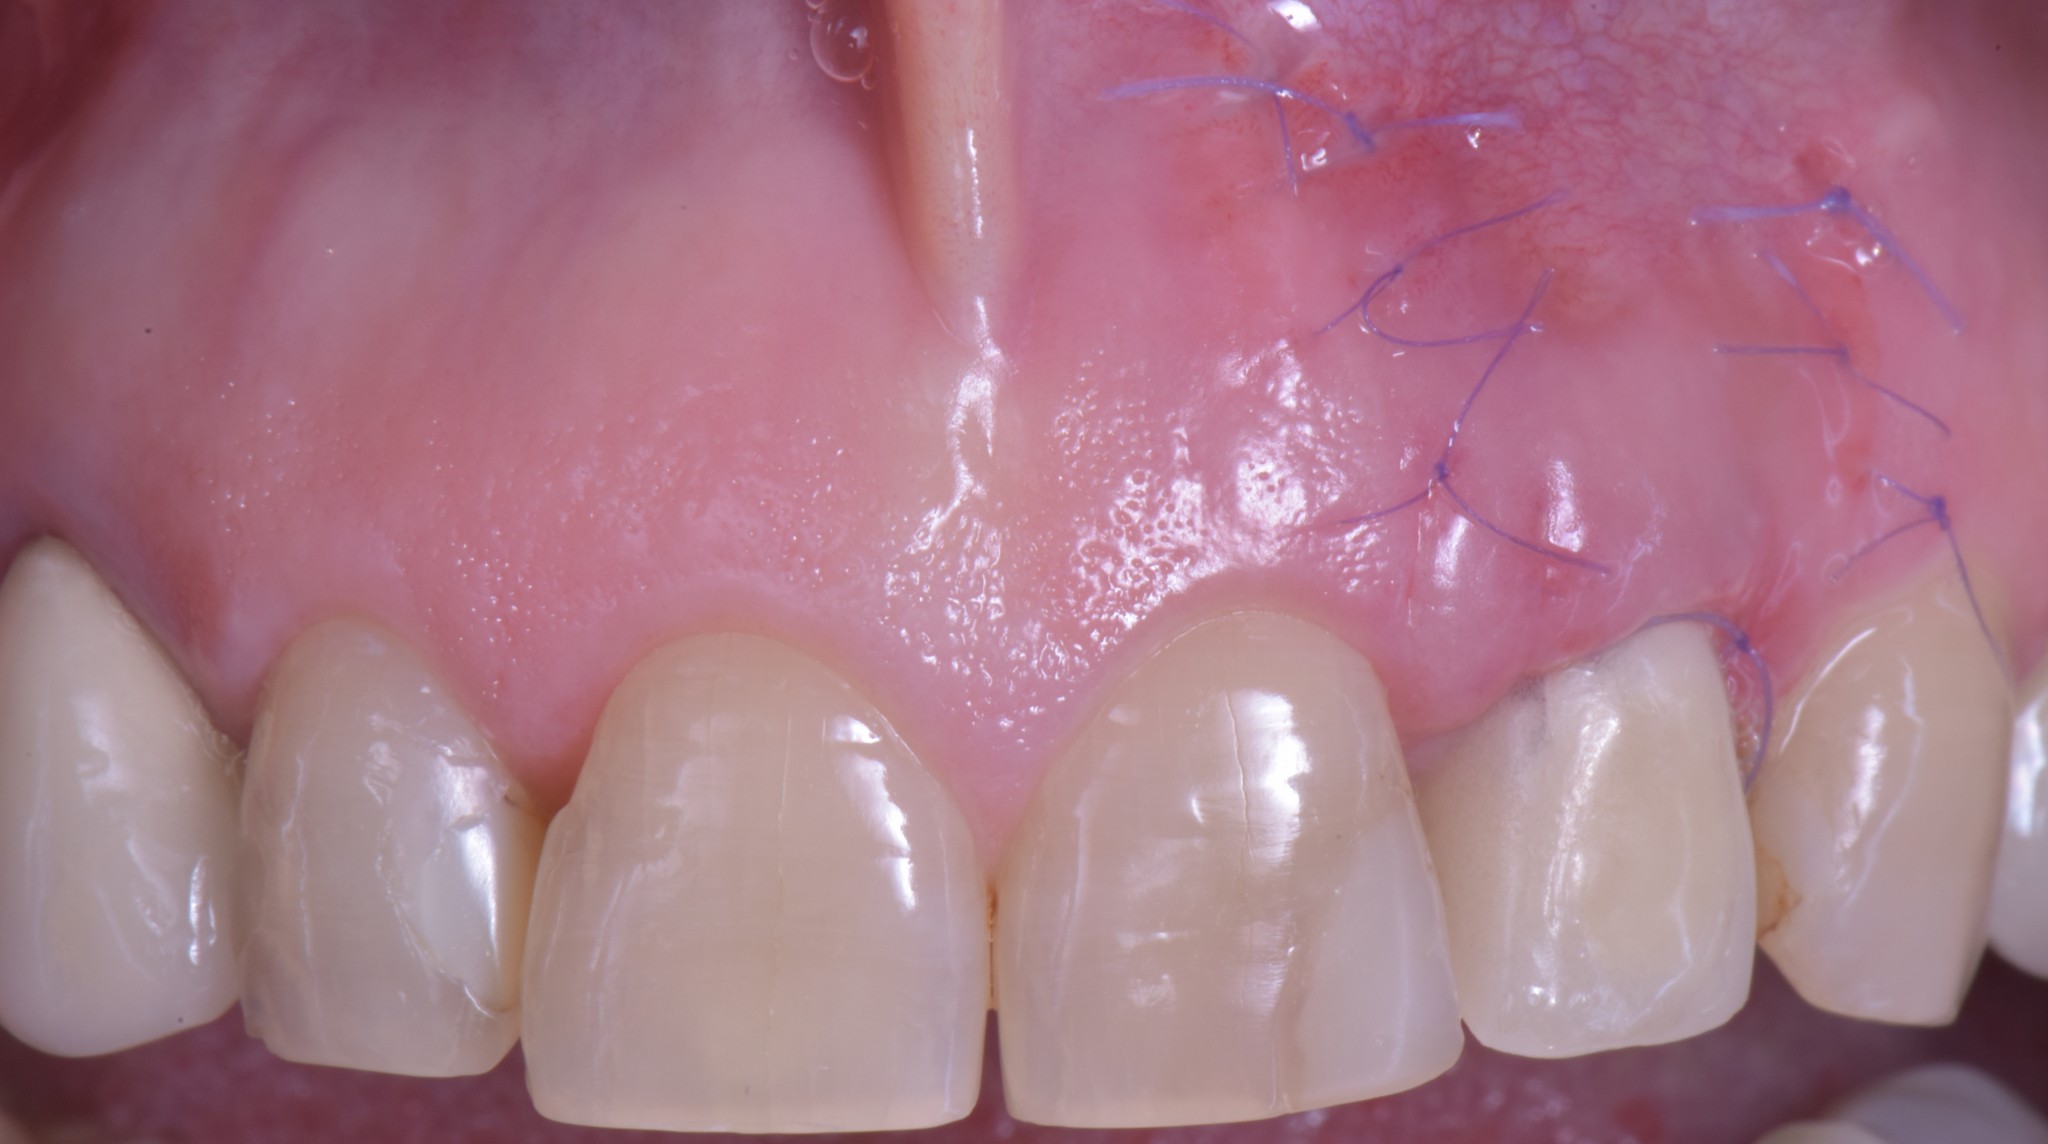

La fistola ed il fastidio persistente di Rosetta li risolviamo in pochi giorni con una riabilitazione provvisoria adeguata.

E quando il tessuto gengivale è di nuovo sano risolviamo il problema estetico. Con un intervento che mi ha richiesto un’oretta solo perché ho dovuto fare una ripresa sensazionale in 4K dove si vedono pure le cellule, ma se mi fossi accontentato di qualche foto ci avrei messo poco più di mezz’ora. Questo non perché io sono veloce ma perché è una chirurgia smart, una chirurgia poco invasiva.

Ti mostro la foto a sette giorni per due motivi.

- La bellezza di una chirurgia si valuta dalla guarigione a sette giorni. Se aspetti 2 anni, alla fine anche una chirurgia di merda guarisce.

- Ho operato la paziente 7 giorni fa e non ho foto più recenti ma penso che concorderai con me che dopo una guarigione così difficilmente avremo delle sorprese.